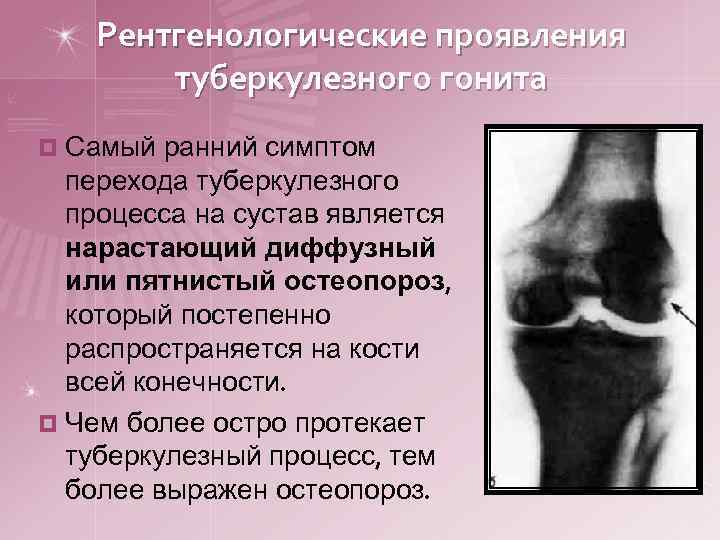

Рентгенологические проявления туберкулезного гонита ¤ Самый ранний симптом перехода туберкулезного процесса на сустав является нарастающий диффузный или пятнистый остеопороз, который постепенно распространяется на кости всей конечности. ¤ Чем более остро протекает туберкулезный процесс, тем более выражен остеопороз.